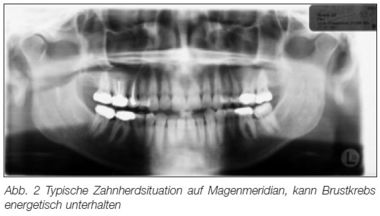

Nicht prüfbaren Berichten aus dem Internet zufolge sollen alle Krebspatienten, die in der Paracelsus-Klinik aufgenommen werden, zunächst auf den Zustand ihrer Zähne hin untersucht werden. Dazu verfügt die Klinik über eine eigene zahnärztliche Untersuchungsmöglichkeit. Nach nicht prüfbaren Angaben sollen bei Krebspatienten Wurzelfüllungen entfernt werden.[16]

Nach unveröffentlichten Angaben von Rau habe er herausgefunden, dass bei 147 von 150 Patientinnen mit Brustkrebs ein oder mehrere Zähne auf dem Meridian des Tumors lägen.